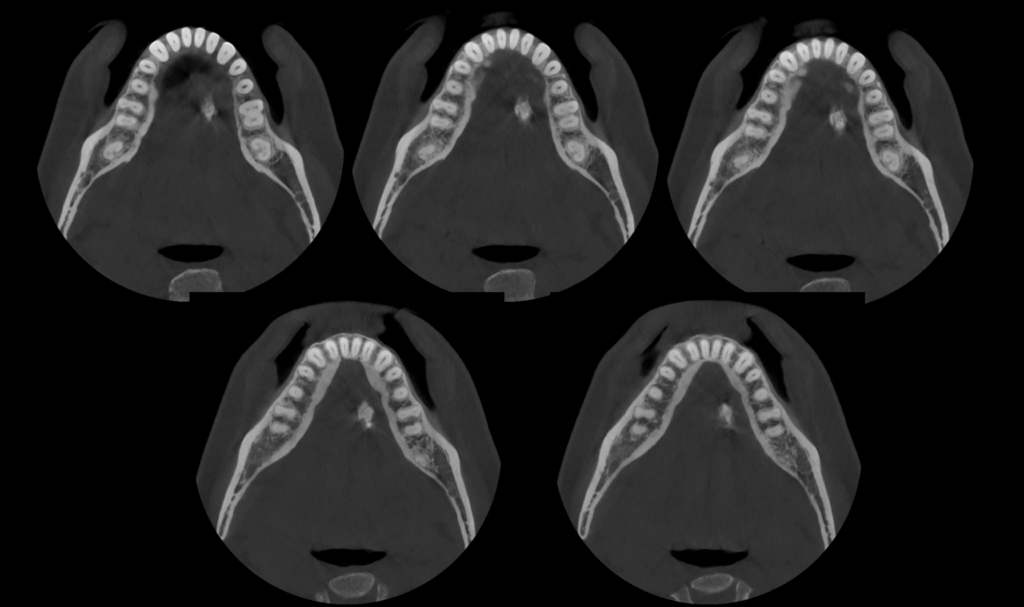

A la evaluación de la tomografía de campo mediano (10 x 10) se observa una imagen hiperdensa que no se evidencia en la radiografía, de forma irregular y limites definidos localizada en tejido blando a nivel de piso de boca y de las piezas 36 y 35 compatible con sialolito submandibular.

RECONSTRUCCIÓN 3D